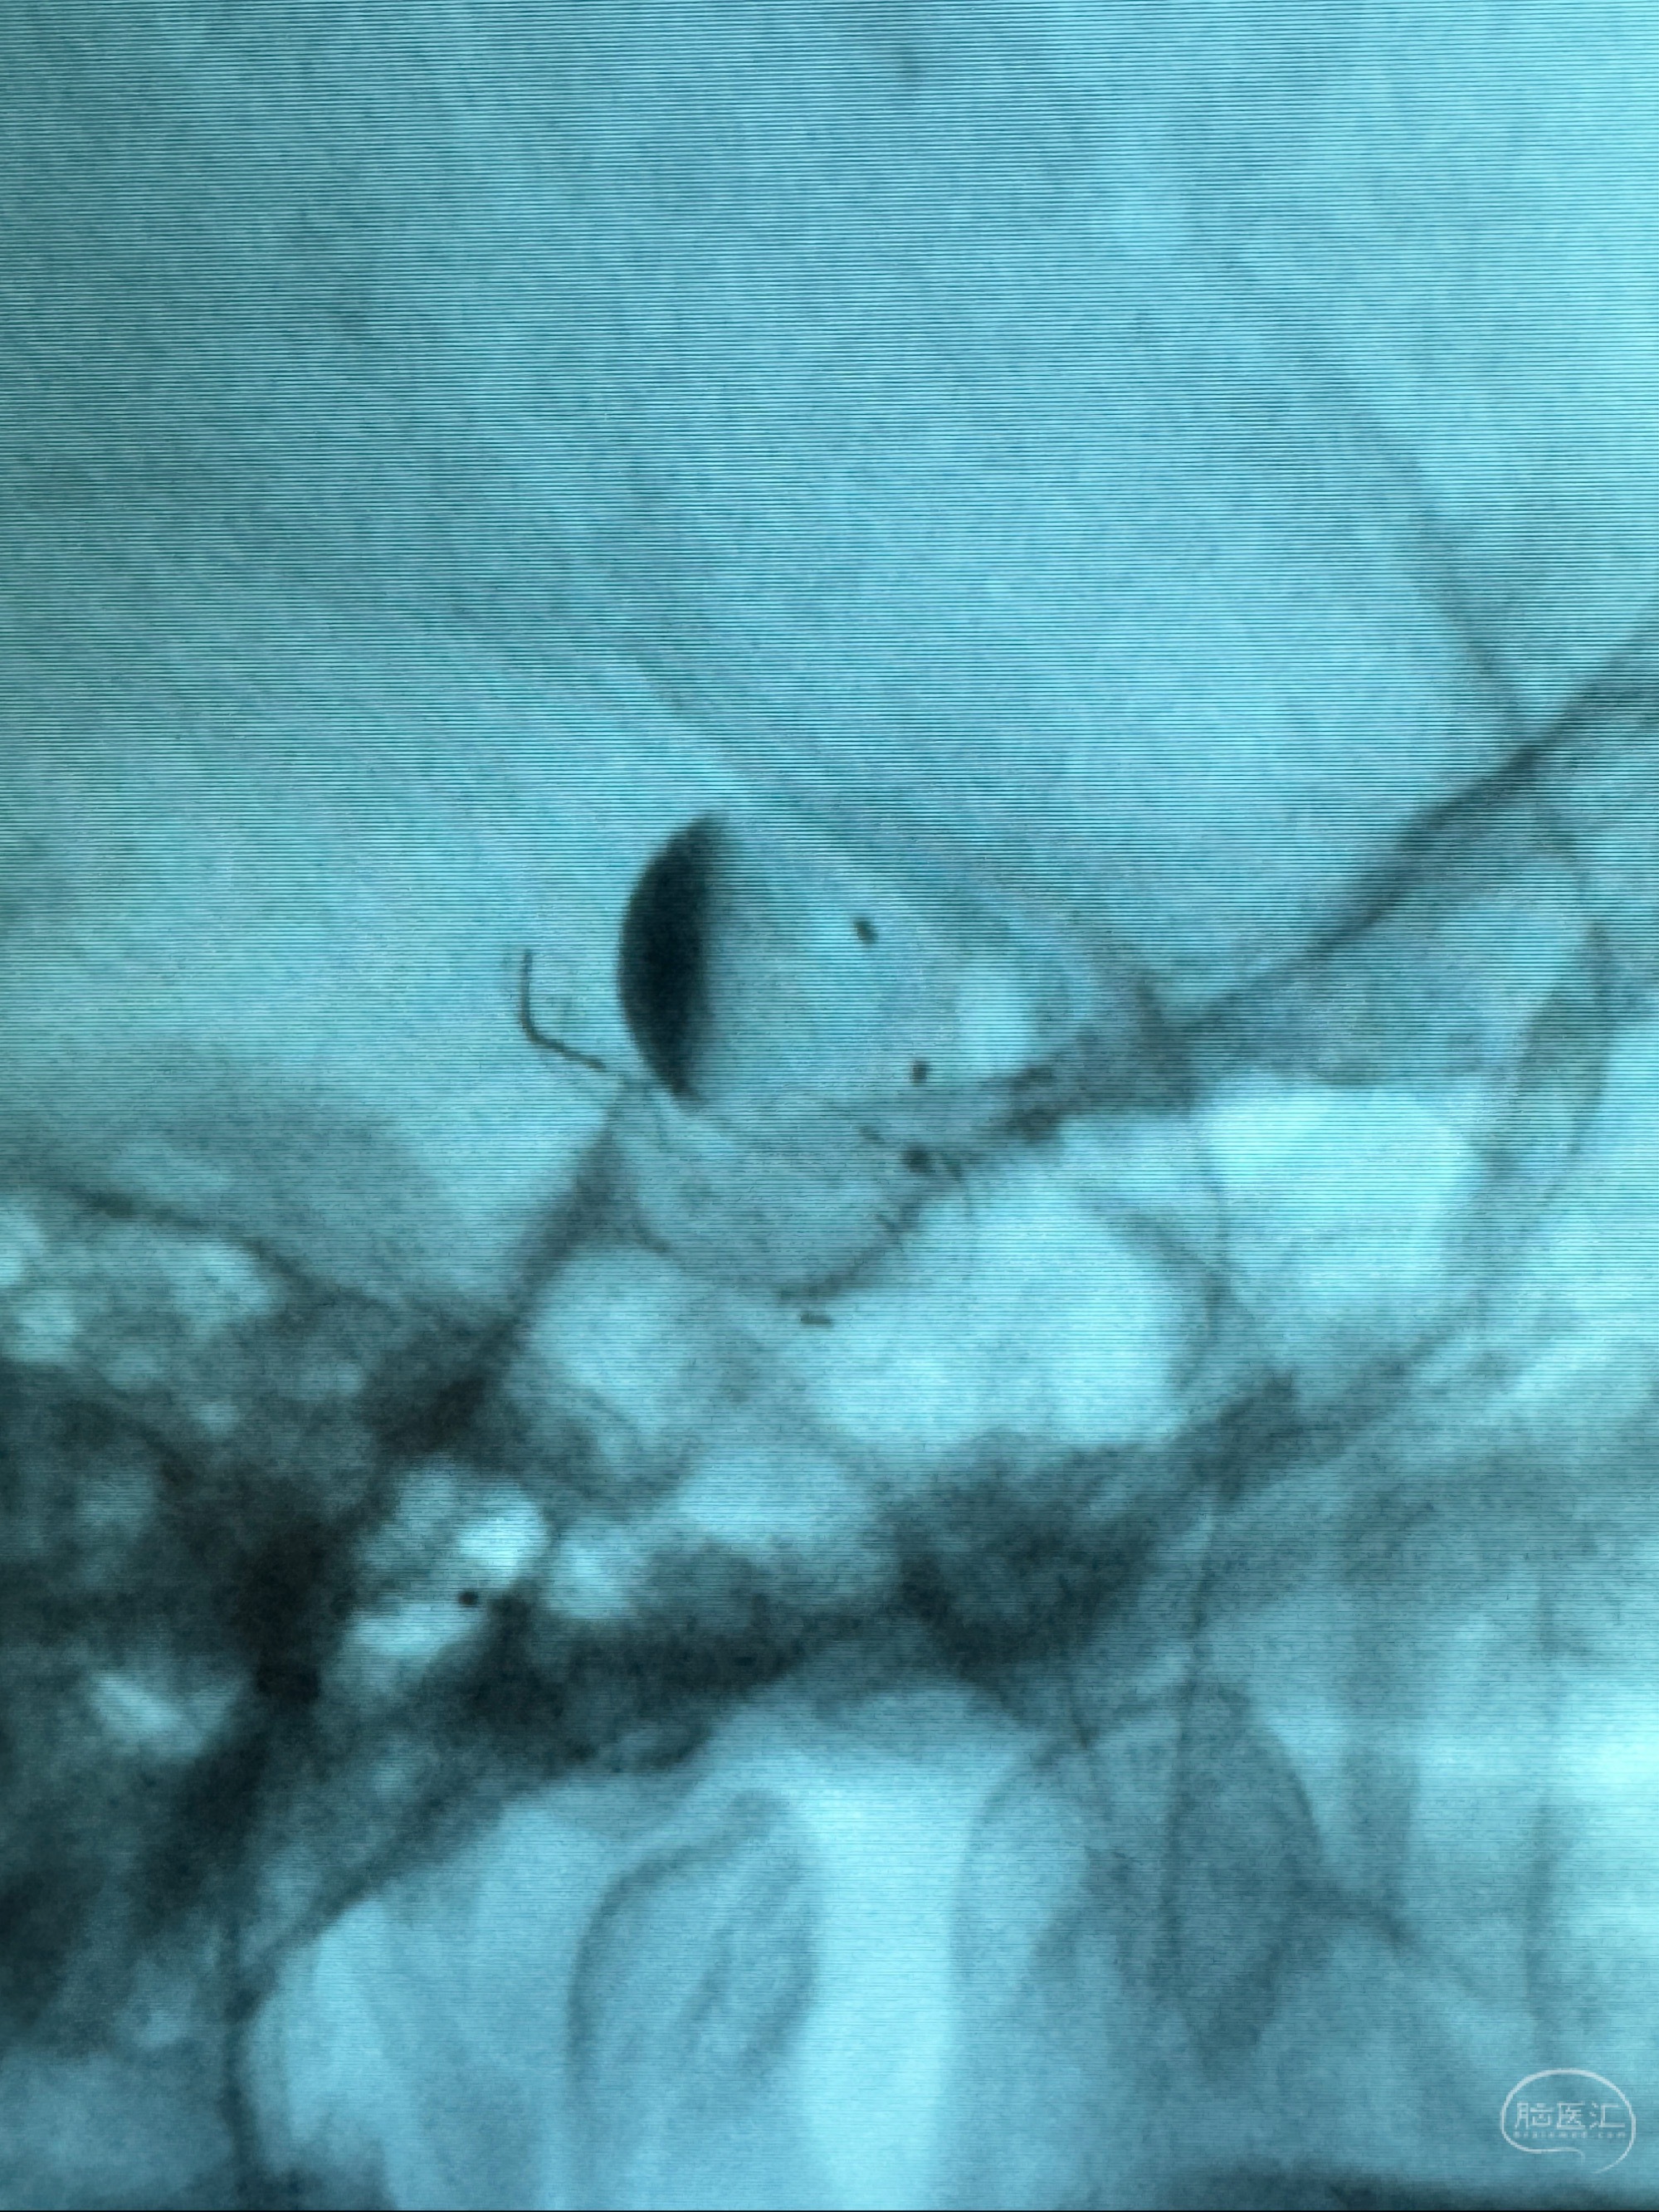

2023-12-08外院DSA:右侧颈眼动脉瘤,约13*12mm大小,压颈试验显示左右向及后向前代偿可

旋转3D展示动脉瘤局部的血管构筑

测量动脉瘤的大小:16*13.8*7.6mm大小,较原先变大,考虑双抗后瘤内血栓溶解可能

观察动脉瘤腔内的血流动力学情况